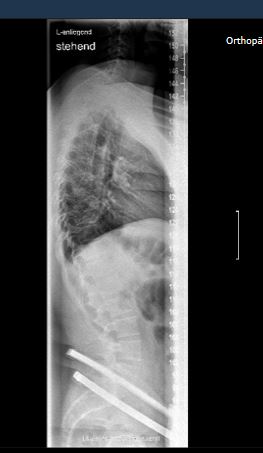

Am Freitag war ich im König-Ludwig-Haus in WÜ wegen eines Fußproblems. Aber sie wollten eine komplette WS-Ganzaufnahme im Stand. 2 Ebenen.. Das Bild wo ihr seht ist akutell von Freitag. dem 04.11. Leider sagte die Ärztin nur dass man dies auf einem MRT nicht so deutlich sehen würde. Und nur dass man es konservativ behandelt. Der niedergelassene hat immer im STEHEN geröntgt. Nehme schmerzmittel mache übungen rehasport an geräten ZNS Bobath und normale KG übungen zU hAUSE

- WS_DM.JPG (29.44 KiB) 5897 mal betrachtet

Seitliches Bild kann ich gerne noch hochladen Ich meine wenn ich nicht im König Ludwig Haus bei Spezialisten war, dann weiß ich auch nicht.. Sie sind eines der besten Kliniken Deutschlands. Seit über 100 Jahren erfahren in dem Bereich der Orthopädie Tumororthopädie, etc.... Man sagte mir halt leider nur dass es gering ist und bei einem Kernspint kaum zu erkennen wäre. (Die Seitabweichung).

Die Physios meinen ich habe eine Hyperlordose, die mir mehr schmerzen macht.

- WS SEITLICH.JPG (21.01 KiB) 5875 mal betrachtet